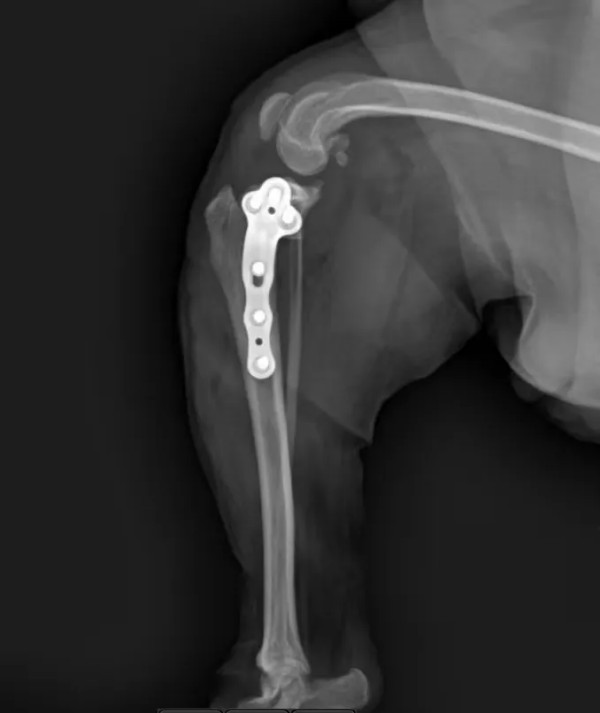

选用2.0型号宠多助TPLO-L骨板,术前TPA=30角°,应用10mm锯片,移动距离4.5mm

术后X光片